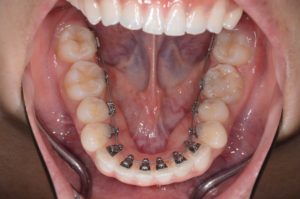

Q6. 裏側矯正(舌側矯正)の特徴は?

A. 装置が見えにくい反面、高度な技術が必要です。

裏側矯正は審美性に優れていますが、発音への影響や装置調整の難しさがあります。

そのため、十分な経験を持つ歯科医師による治療が重要とされています。